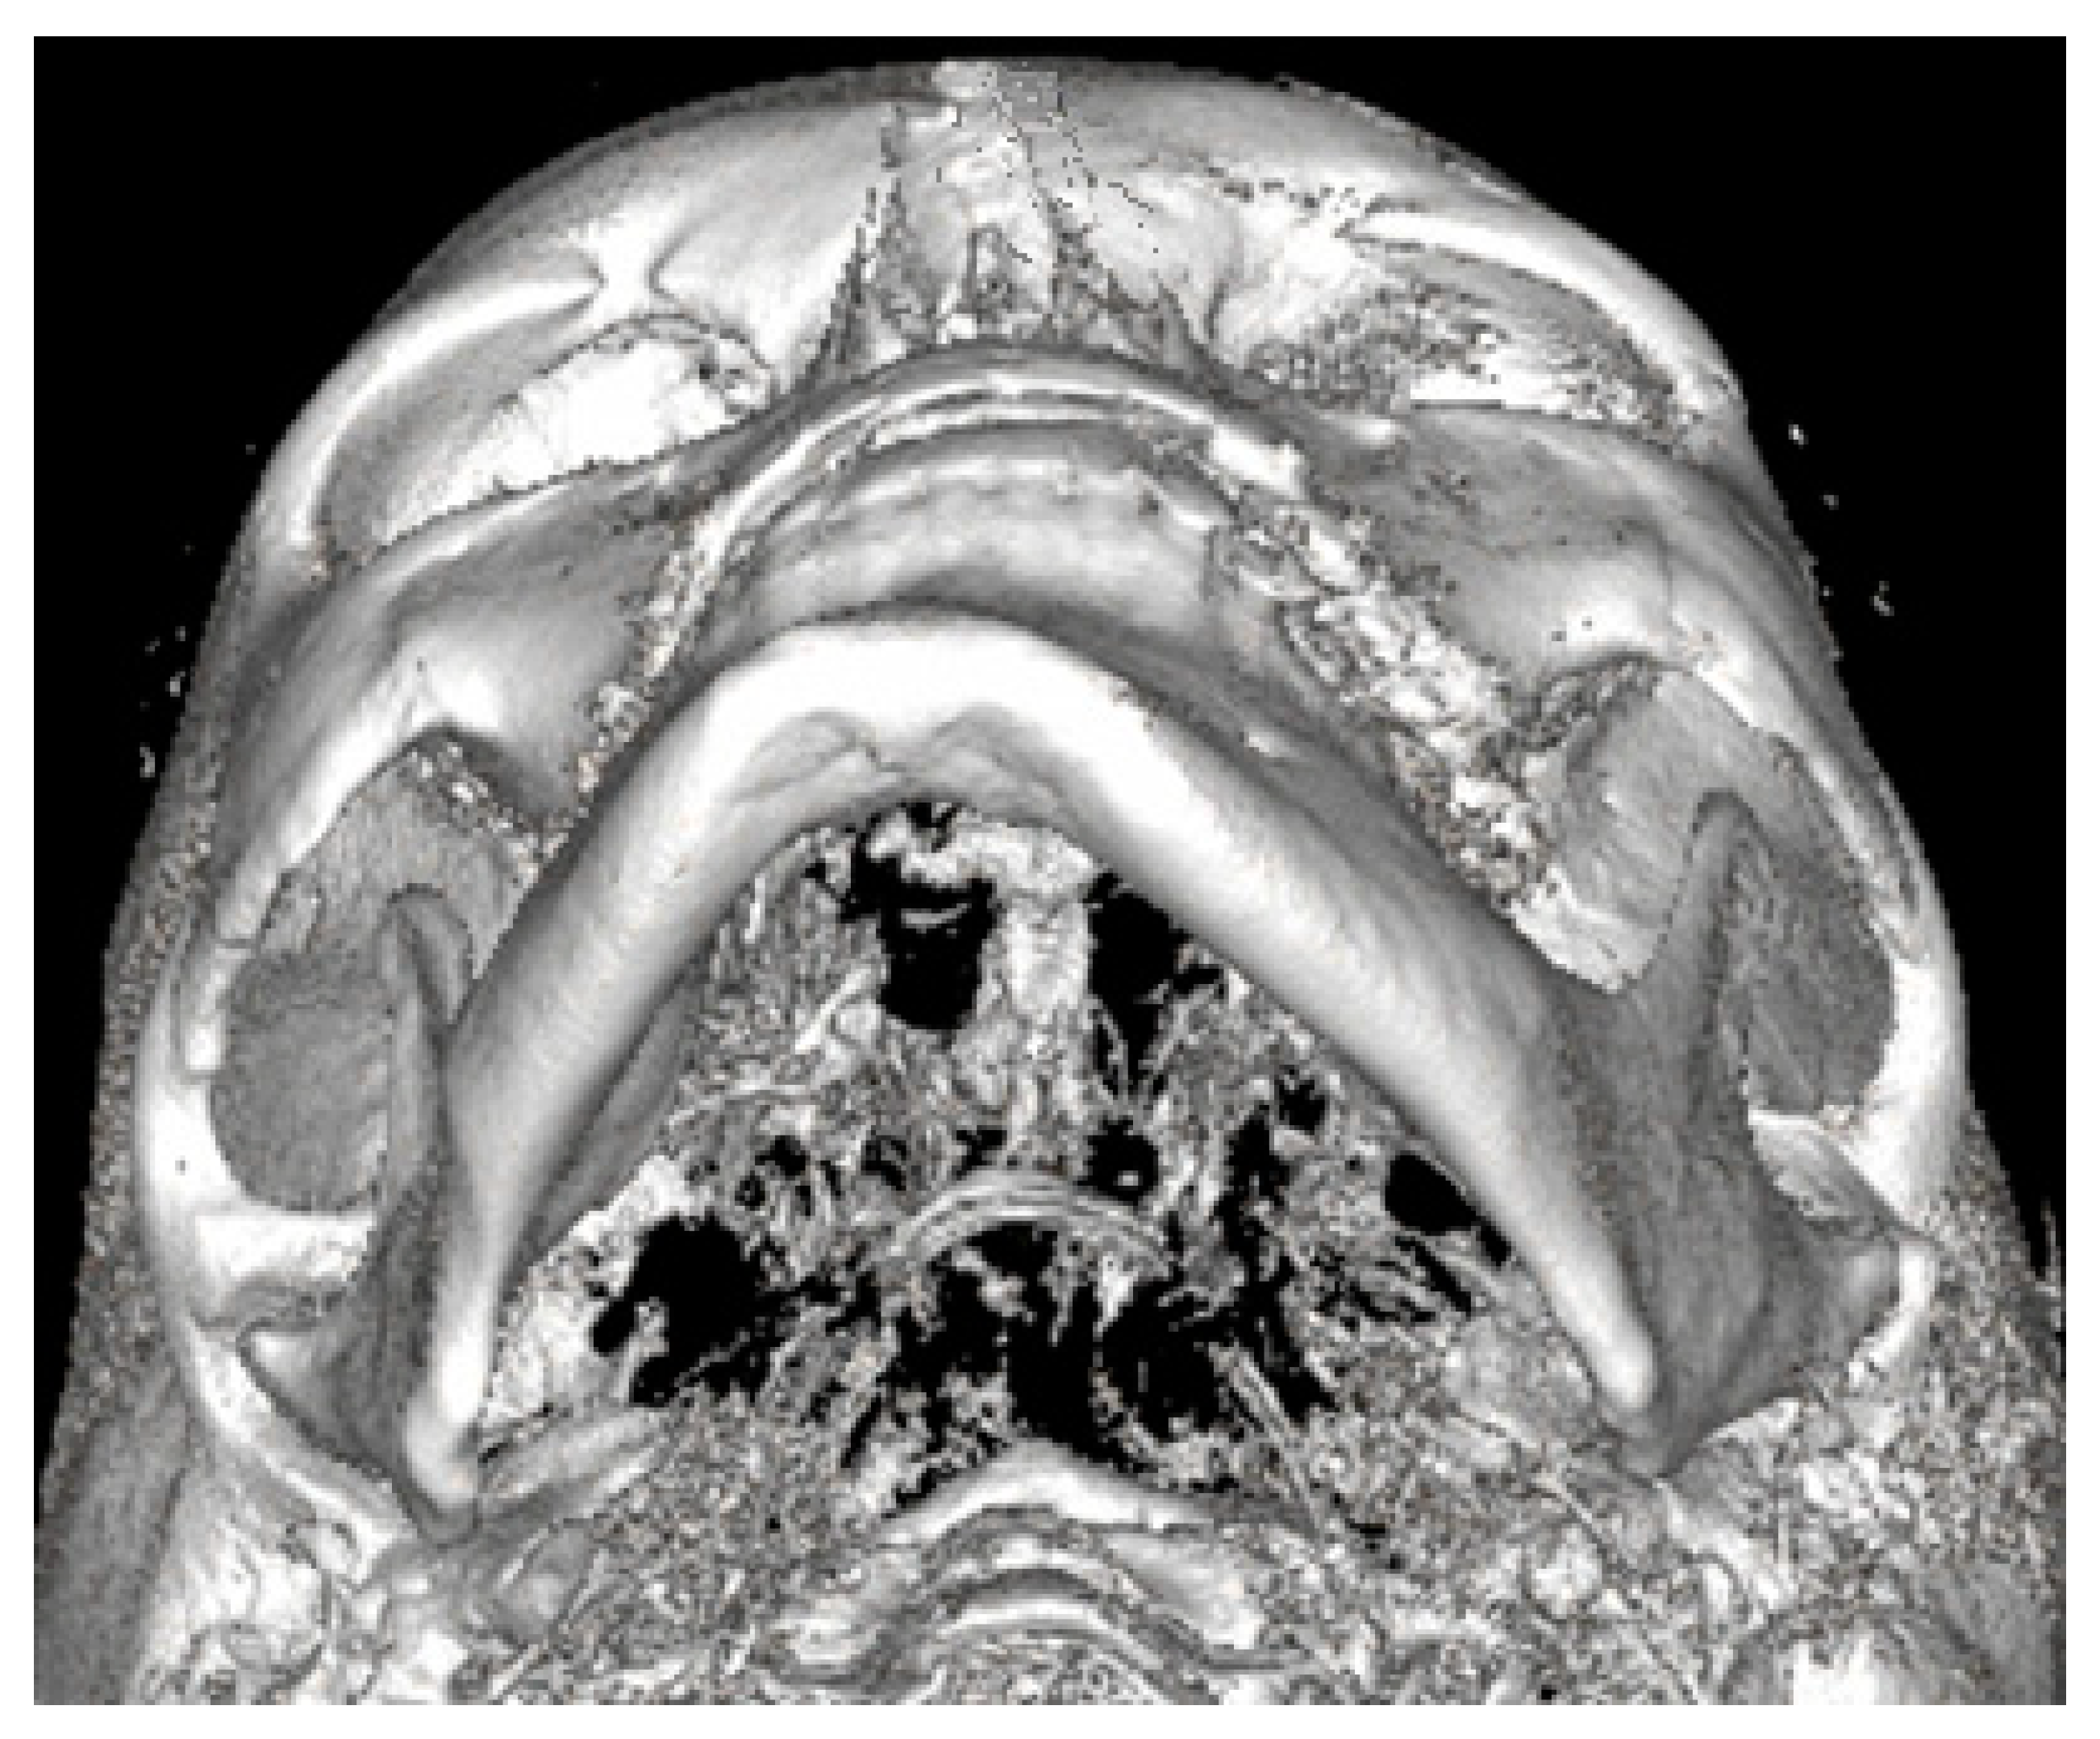

Figure 4.

LDCT semi-axial view on the deviated mandible. Except for chin deviation, elongation of left mandibular basis, and slight Go-point asymmetry, the mandibular body is not enlarged nor presents overgrowth in a significant diameter.

Both panoramic radiographs and LDCT evaluations are important for any surgery planning. There is a possibility to estimate the shape and position of the mandibular canal while tracing its course on 3D evaluation and then estimating the degree of surgery in MIB (Figure 3 and Figure 4). Secondly, based on the studied patients’ data, the authors also include that the position of the mental foramina, chin deviation, and Go reference points described herein are valuable reference points for future surgical planning. Another important feature possible to estimate on 3D-LDCT is the scope of mandibular basis overgrowth in three dimensions.